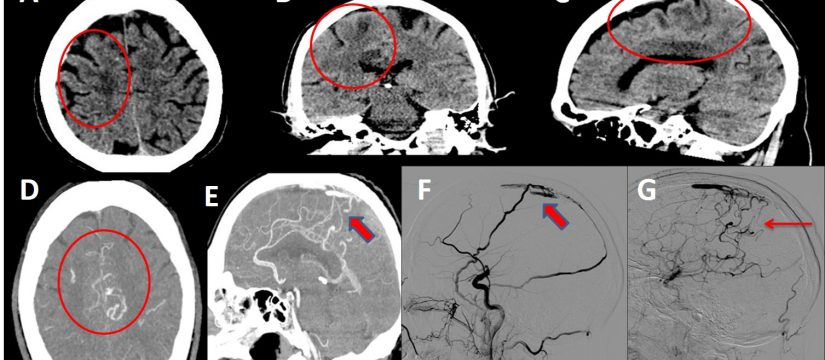

Historia Clínica

Varón de 40 años con esclerosis múltiple remitente-recurrente ya conocida, que consulta por disartria de varios días de evolución.